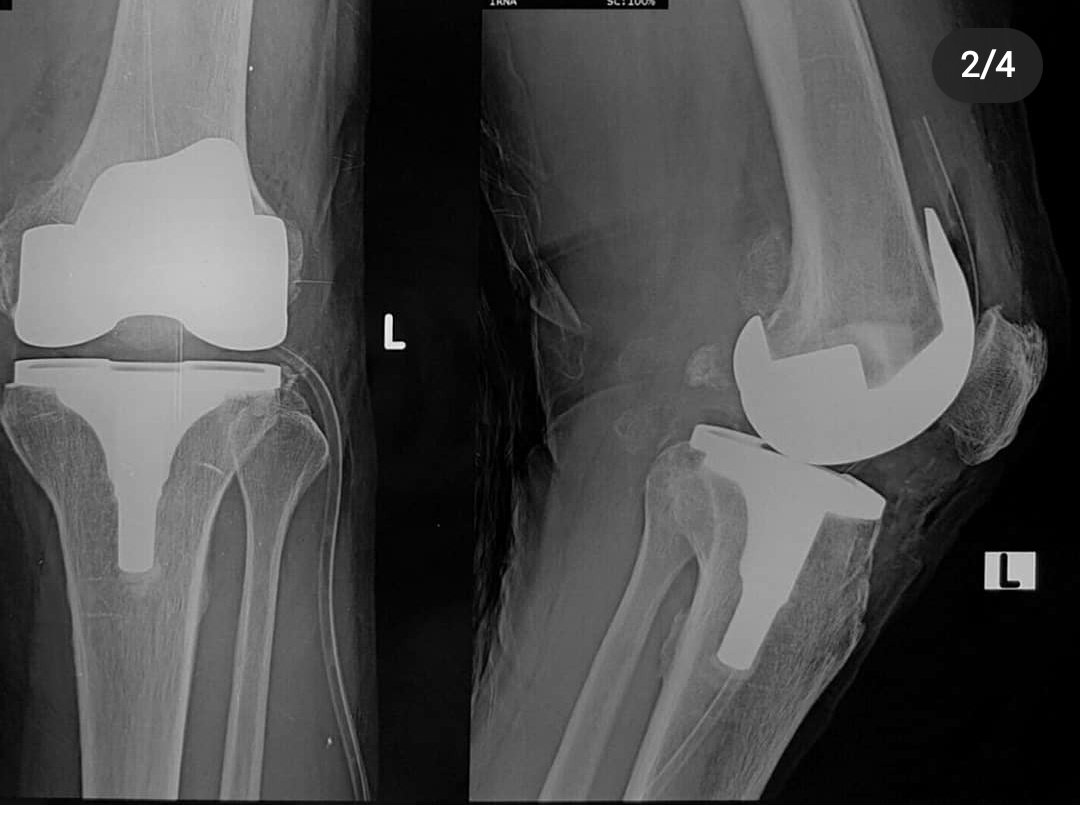

pada kasus yang berat,obat&semua mcm cara ud ga bisa lagi utk mengurangi sakit pasien,ngapa2in sakit, kasusnya uda parah, pada kasus yg sudah seperti ini, pilihan yg paling tepat adalah operasi, operasinya adalah operasi TKR (total knee replacement ) ,atau penggantian sendi lutut

Operasi ini kalo berobat mandiri lumayan mahal,utk satu lutut bisa sekitar 50 - 100 jt abisnya(bisa lebi juga tergantung operasi di mana sama siapa)

TAPII

Tindakan ini bisa DITANGGUNG full kok sama @BPJSKesehatanRI

Jadi akses utk operasi mahal sekarang bisa dijangkau semua org!

Selain itu, semua aspek pengobatan osteoarthritis itu jg semua ditanggung sama BPJS

mulai dari :

- obat dan kontrol(bisa seumur hidup lho ga sembuh)

- suntik

- fisioterapi

- bahkan sampai dgn operasi .

Jadi jgn lupa utk punya bpjs yaaa karena benefitnya besar bgt